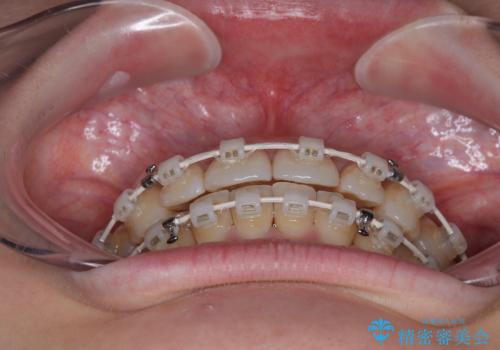

上下前歯のデコボコ ワイヤー装置で楽ちん矯正治療

- 審美装置

- 1年3ヶ月

お仕事柄、マウスピース装着は困難とのことで、表側のワイヤー矯正にて治療を行うこととしました。

デコボコ解消の際に、前歯が前突するリスクがあったため、舌突出癖の改善と、アンカースクリューによる加強固定を行うこととしました。